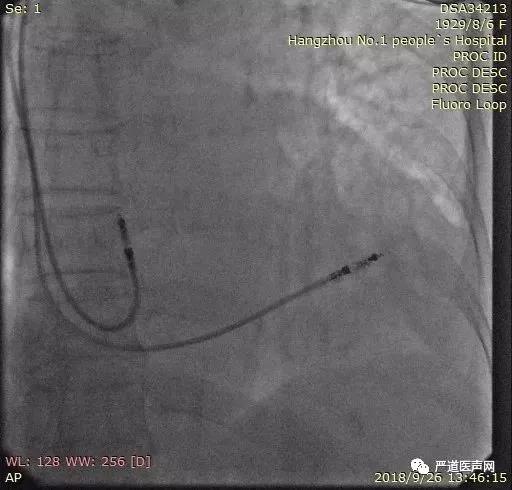

双主动电极植入手术演示

术中心房多次换位尝试,阈值始终偏高,许轶洲主任积极与学员分享交流处理策略,调整钢丝塑性,最终以阈值1.0v以下完成手术。